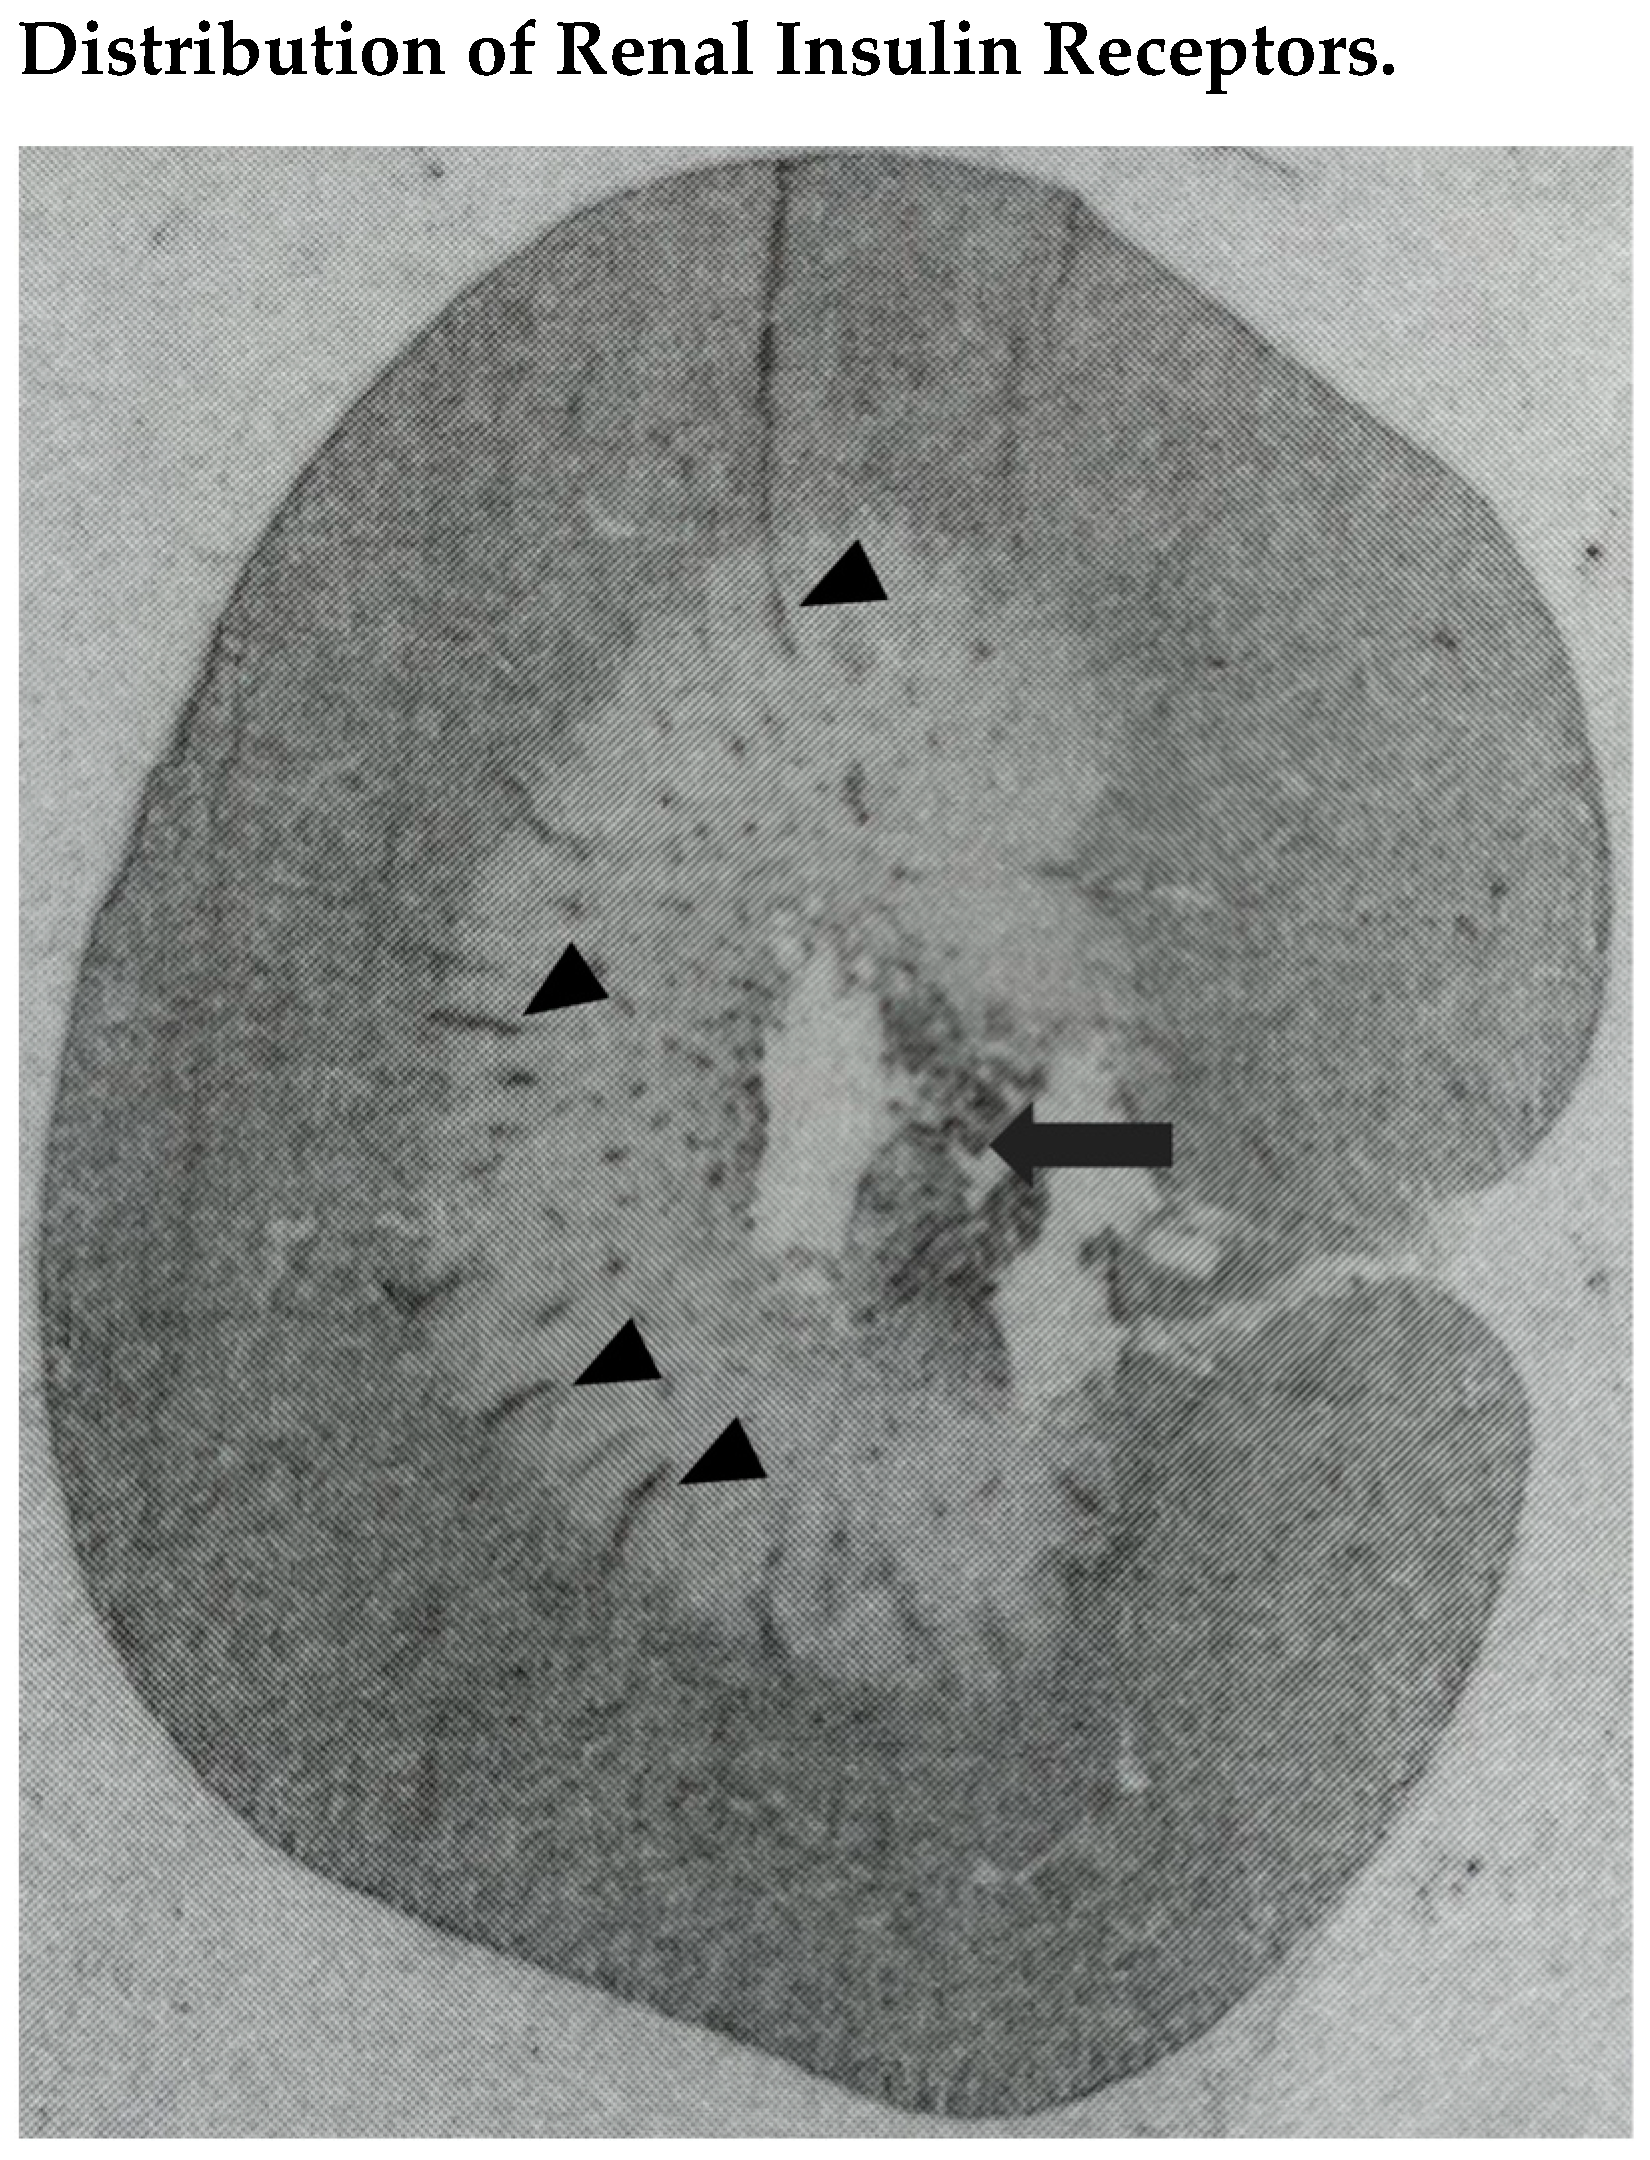

- Butlen, D.; Vadrot, S.; Roseau, S.; Morel, F. Insulin receptors along the rat nephron: [125I] insulin binding in microdissected glomeruli and tubules. Pflügers Arch. 1988, 412, 604–612. [Google Scholar] [CrossRef]

- Sechi, L.A.; De Carli, S.; Bartoli, E. In situ characterization of renal insulin receptors in the rat. J. Recept. Res. 1994, 14, 347–356. [Google Scholar] [CrossRef]